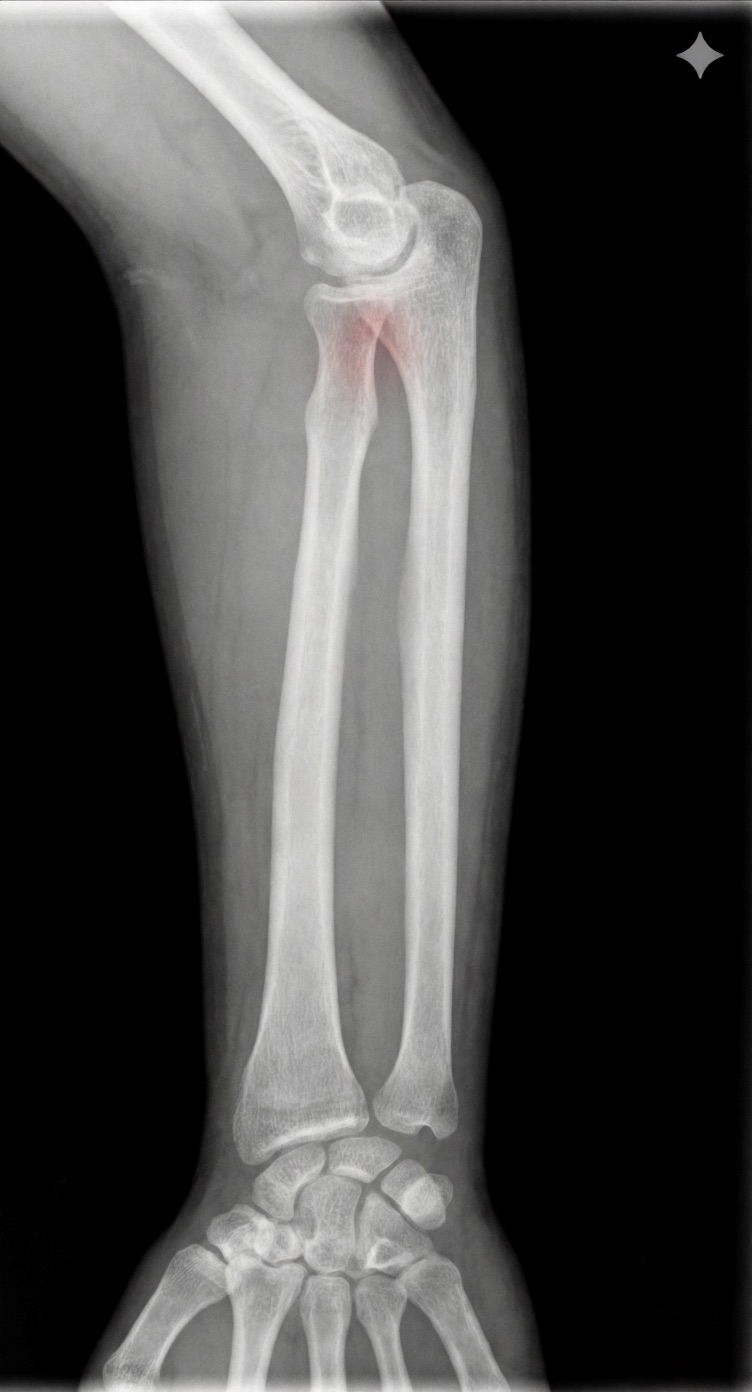

アートや写真の編集用に設計されたFlux Kontextのようなモデルを、医療画像、たとえば「単純な」骨折の赤色マーキングに使用できるか?

即答:面白い結果を出すが、過剰に反応し、医療ツールとしては信頼性に欠ける。これはアイデアを試すためのプロトタイプに過ぎない。

Civitai用に作成した、100% AI生成の合成ミニデータセット(健康なX線10枚、骨折のあるX線10枚)でテスト:

- 健康な骨での偽陽性:100%

- 骨折検出:≈ 45%

有効な用途

- 医療画像におけるAIプロトタイプやテスト

- X線の「疑わしい」領域を視覚的に目立たせる(実験的・創造的アート、エキゾチックなツール xD)

- 感度 vs 偽陽性のバランスを実験するための教育的・実験的素材